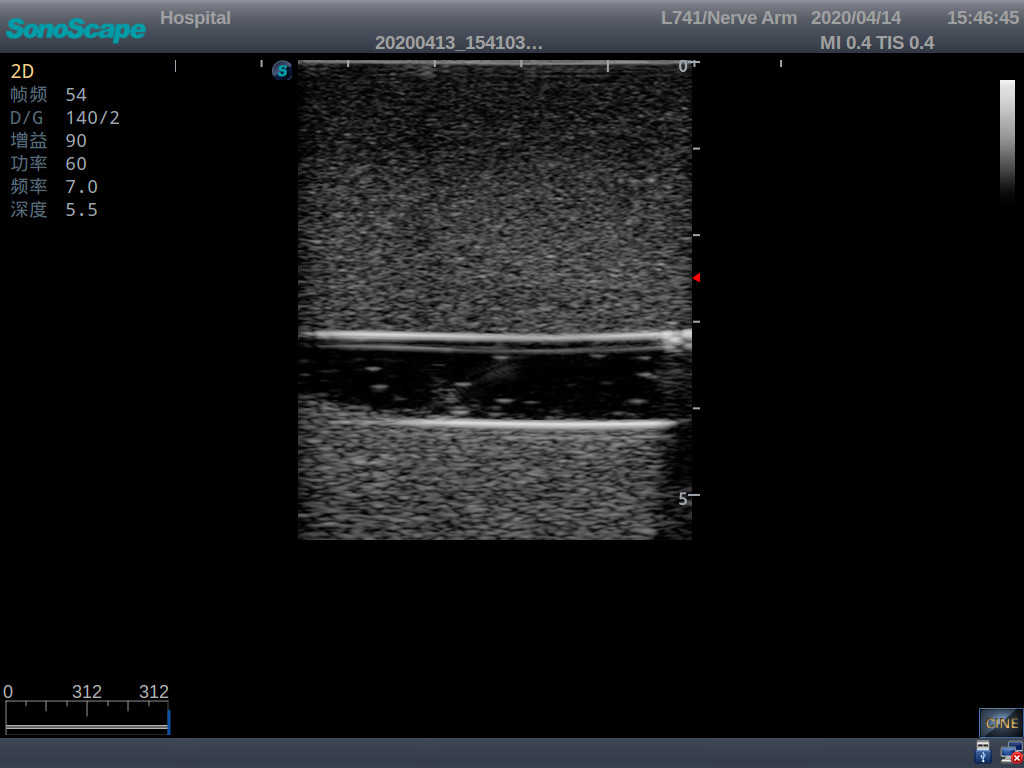

Model TYE1510.1

Product size(mm) 700×500×160

It is a model covering up from lobulus auriculae plane to the umbilical plane, and it has anatomical structures like clavicle, rib, sternocleidomastoid, jugular vein and basilic vein.

2)   It can be used by real ultrasound machines

3)   Clear and real images of the tissues and organs (basilic vein and superior vena cava)

5)   Observe the guide wire marches

6)   Detect whether the catheter is properly placed